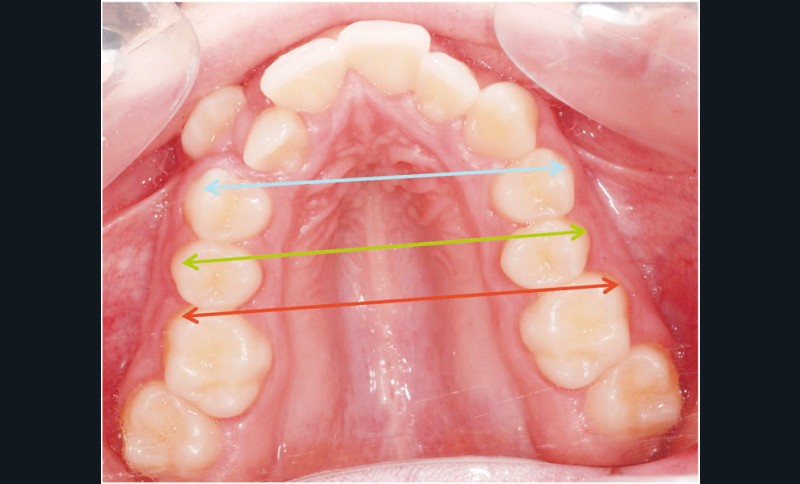

Le cas d’Anthony âgé de 11 ans et 7 mois qui présente une endomaxillie bilatérale associée à un léger encombrement mandibulaire dans un contexte de classe I squelettique hyperdivergente (fig. 1 à 10) est très représentatif de ce que peuvent apporter les forces légères appliquées aux alvéoles dentaires tout en intégrant des torques spécifiques qui permettent de contrôler parfaitement l’orientation radiculaire (fig. 11 à 29).

Le système laisse beaucoup de liberté dans l’interface entre bracket et arc : la vascularisation, et donc le recrutement cellulaire et la reconstruction osseuse s’en trouvent améliorés, la mise en place de l’occlusion se fait sous le contrôle de la matrice fonctionnelle, car les forces engagées restent en dessous de la puissance des forces masticatrices notamment.